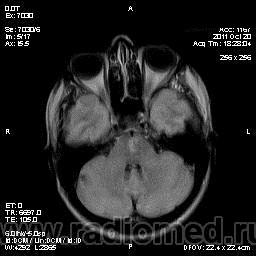

Центральный понтинный миелинолиз

Центральный понтинный миелинолиз — это особая форма демиелинизирующего процесса в области моста мозга, развивающаяся при быстрой коррекции гипонатриемии любой этиологии. Состояние впервые было описано при хроническом алкоголизме R. Adams в 1959 г. как осмотический демиелинизирующий синдром. Название «центральный понтинный миелинолиз» (ЦПМ) он получил позднее, когда был выявлен и при разных патологических состояниях — почечной недостаточности, сахарном диабете, булимии, печеночной недостаточности, аденоме гипофиза, вирусных инфекциях, системной красной волчанке, дефекте обмена мочевины, гастроэнтерите, длительной терапии диуретиками 1. Общим для них является наличие обменных сдвигов изменений водно-солевого обмена. ЦПМ встречается не только у взрослых, но и у детей.

Морфологически ЦПМ характеризуется распадом миелина в центральной части моста мозга с распространением на все проводящие пути за исключением латеральных отделов. Собственно аксоны, лишаясь миелиновой оболочки, не повреждаются. Развитие миелинолиза в других областях мозга получило название «экстрапонтинный миелинолиз» (ЭПМ). При ЭПМ очаги демиелинизации обнаруживаются в ножках мозга, зрительном бугре, мозолистом теле, не сопровождаясь воспалительной реакцией как при рассеянном склерозе.

На РКТ билатерально выявляются очаги пониженной плотности в мосту и других участках мозга, не сопровождающиеся контрастным усилением. Но следует заметить, что компьютерная томография не всегда способна выявить очаги поражения при данных патологических состояниях, особенно в его ранних стадиях.

МРТ в Т2W позволяет выявить равномерное повышение сигнала в зонах поражения мозга, иногда сопровождающееся снижением сигнала в зоне кортико-спинальных путей; в Т1W интенсивность сигнала в очагах поражения снижена, без признаков перифокального отека или объемного воздействия 1. Участок поражения моста визуализируется в виде овальной зоны на сагиттальных и аксиальных срезах и в форме крыльев летучей мыши на коронарных срезах. Покрышка моста и его вентролатеральные отделы не поражаются. Иногда очаг распространяется на средний мозг или на другие (экстрапонтинные) зоны: перивентрикулярное белое вещество, внутренняя и наружная капсулы, подкорковые узлы, таламус, коленчатые тела, а также белое вещество вблизи коры полушарий мозга и мозжечка. Признаки поражения на МРТ могут исчезать после клинического выздоровления.

Дифференциальный диагноз при рассматриваемой патологии должен проводиться прежде всего с опухолями мозга (глиомы, метастазы). Нужно иметь в виду также инсульты, рассеянный склероз, энцефалит и острый рассеянный энцефаломиелит, но эти заболевания обычно визуализируются в виде более диффузных очагов и отличаются от ЦПМ и ЭПМ клинически; паразитарные поражения моста и базальных ганглиев не бывают столь симметричными.